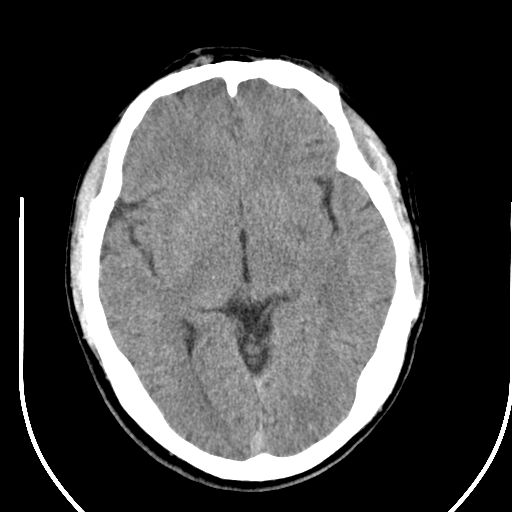

标题: CT25423:头部外伤意外发现右顶叶??? [打印本页]

标题: CT25423:头部外伤意外发现右顶叶???

ct值约13hu。

边缘清晰,没有占位效应,不像脑沟,结合ct值,软化灶可能吧

与脑沟没关系,小软化灶或陈旧性感染吧!

看样年纪不小了直接报腔梗,当然你要想报软化灶也是一样的

考虑右侧额叶巨腔隙灶;建议必要时行mri检查。